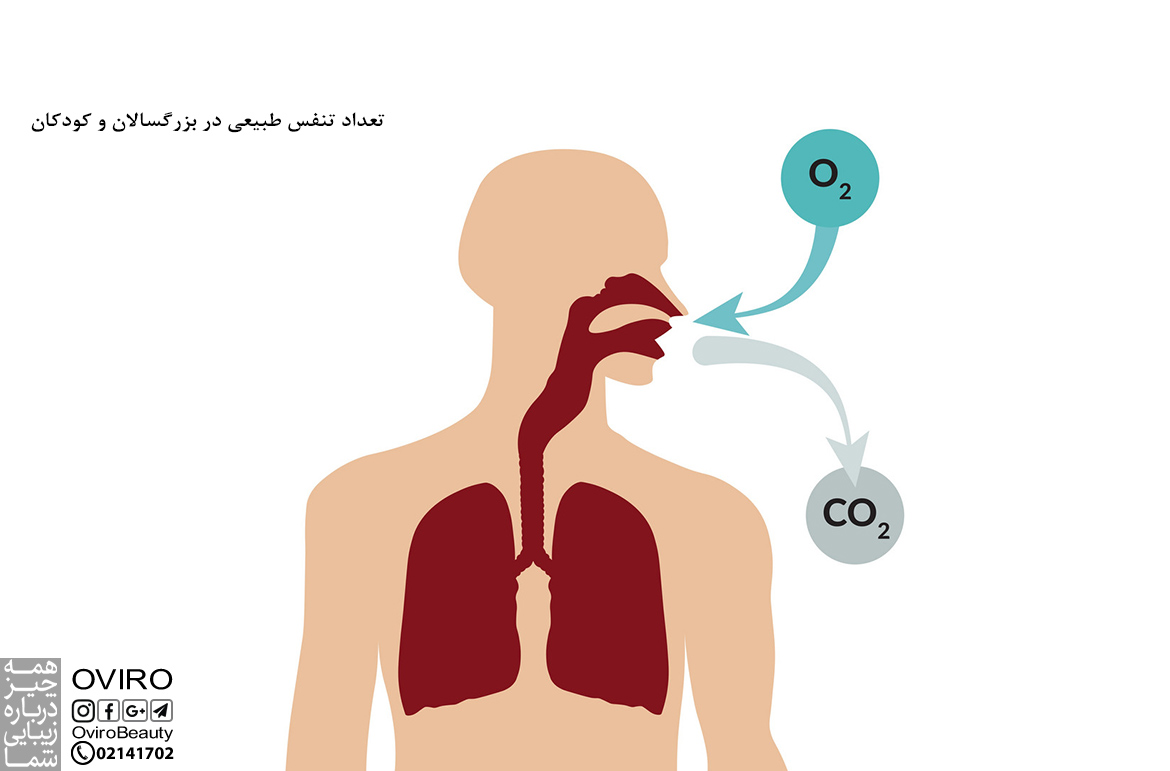

تعداد تنفس طبیعی در بزرگسالان و کودکان

تعداد تنفس طبیعی در بزرگسالان و کودکان متفاوت است؛ نحوه اندازه گیری تعداد تنفس و علت کاهش و افزایش نرخ…